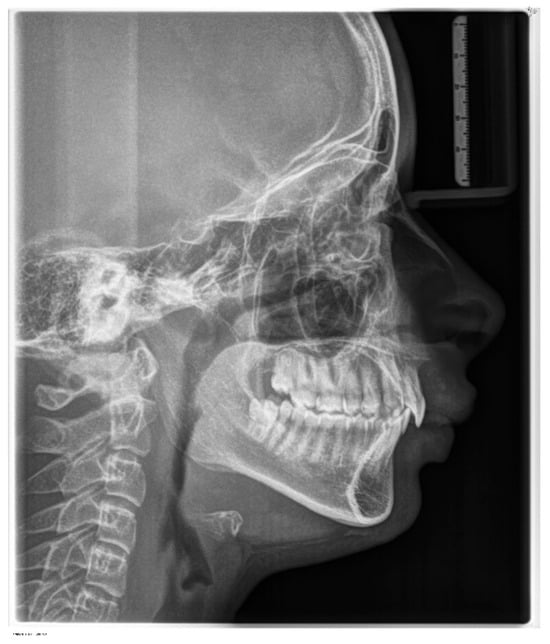

According to latero-lateral teleradiography (Figure 4), she presented with an upper jaw retrusion combined with a lower jaw retrusion relative to the cranium (SNA = 81°, SNB = 73°, Wits appraisal of 7 mm) and a normal facial growth pattern (NS-Sar-ArGo-GoMe = 398.9°) with a normal mandibular plane angle (FMA = 25°, Gonial angle = 120°). Although the skeletal discrepancy was compensated by maxillary incisors’ retrusive inclination (upper incisor to SN = 89.48°, to NA = 1.55 mm) combined with normal mandibular incisors inclination (lower incisor to GoMe = 90°, to NB = 27°), an increased overjet of 15 mm was measured as reported in Table 1. Furthermore, a pretreatment lateral cephalometric radiograph revealed narrow airways.

Figure 4. Pre-treatment lateral cephalometric radiograph.